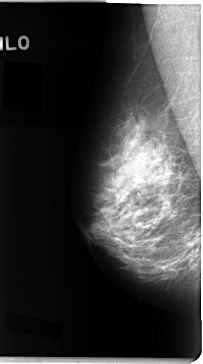

C_0097_1.RIGHT_MLO

RIGHT_CC LINES 4736 PIXELS_PER_LINE 2608 BITS_PER_PIXEL 12 RESOLUTION 50 NON_OVERLAY

RIGHT_MLO LINES 4720 PIXELS_PER_LINE 2632 BITS_PER_PIXEL 12 RESOLUTION 50 NON_OVERLAY